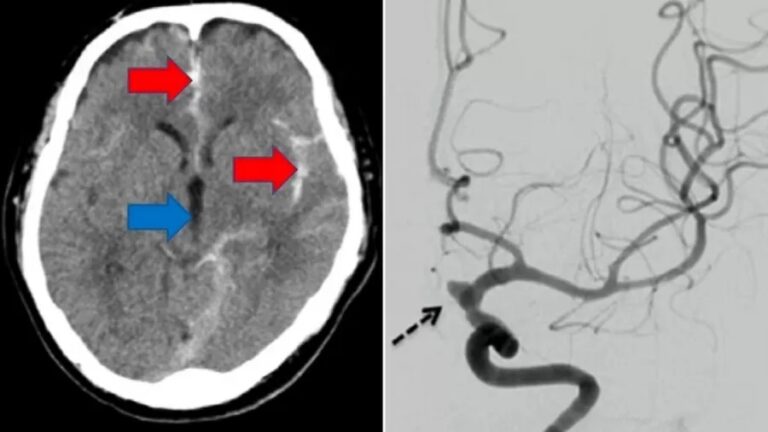

Os médicos que atenderam a emergência suspeitaram que ele teve um derrame durante a masturbação – e uma tomografia computadorizada subsequente confirmou que o homem havia realmente sofrido uma hemorragia subaracnóidea, um tipo de derrame potencialmente fatal.

Esse tipo de derrame é desencadeado por vasos sanguíneos que se rompem no espaço ao redor do cérebro.